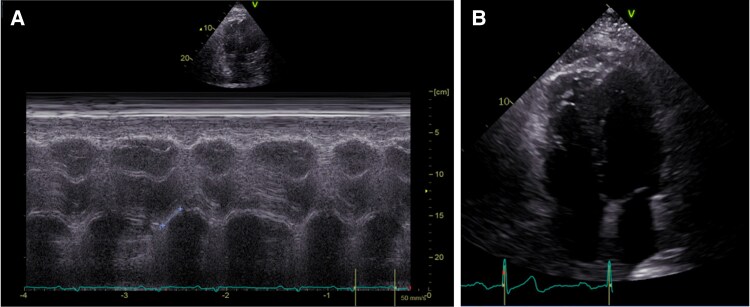

Case summary: A 73-year-old White male was hospitalized in order to perform abdominal surgery. Afterwards, multiple complications led to recurring operations and a prolonged immobilization time. In the aftermath, the patient suffered an in-hospital cardiac arrest and was put on VA-ECMO. A computed tomography pulmonary angiography presented bilateral central PE. Due to contraindications for systemic thrombolysis, successful CDT using a FlowTriever catheter was performed, leading to a reduction of mean pulmonary arterial pressure. ECMO therapy could be terminated in the following days. The patient was eventually discharged without any signs of right heart strain in transthoracic echocardiogram, neurological sequelae or dyspnoea.